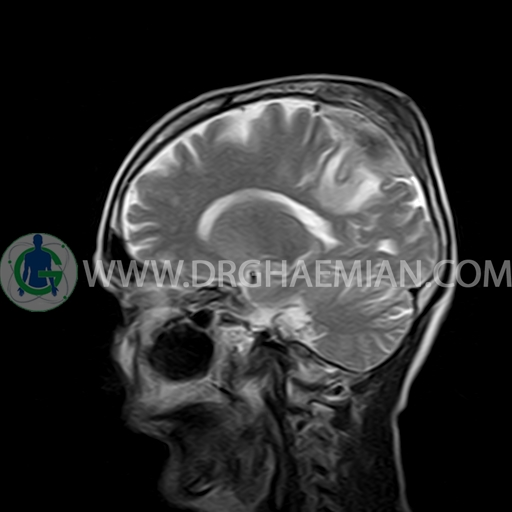

ام آر آی مغز با استفاده آهنربا های قوی و امواج رادیویی تصاویری از مغز و بافت های عصبی پیرامونی آن ایجاد می کند. در این کیس مننژیوم به همراه هیپراستوز استخوانی سمت چپ دیده می شود.

BRAIN MRI

(Without contrast)

Technique:Axial FLAIR, Axial, sagittal, FSE T2, coronal T1 .

a well – defined dural based mass lesion ( 27x55mm ) in left parietal region with signal change in adajacent bone suggestive for meningioma with bone hyperosteosis

mass effect & edema in left parietal lobe

are seen

COMMENT : MRI with contrast is recommended .